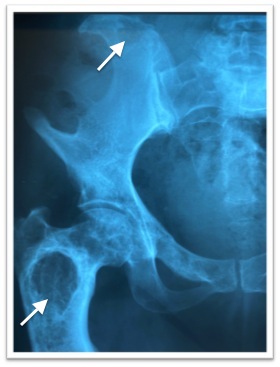

С рождения — обширные пятна цвета «кофе с молоком». В 7 лет отмечен перелом верхней трети правого бедра, через месяц после снятия гипсовой повязки — повторный перелом, находился на скелетном вытяжении. С этого же возраста — деформация нижних конечностей, стал прихрамывать. Повторный осмотр ортопедом в 12 лет в связи с усилившейся хромотой, болью в поясничной области. Выполнены рентгенография и МСКТ костей таза и бедренных костей: деформация бедренных костей по типу пастушьего посоха, очаги фиброзно-кистозной дисплазии, на снимках визуализируются консолидированные переломы правого и левого бедра. Было предложено оперативное лечение после консультации эндокринолога.

На рис. 8 — рентгенограмма костей таза в возрасте 17 лет: очаги ФД в правой бедренной кости. Остеосинтез левой бедренной кости.

Рис. 8. Очаги фиброзной дисплазии в правой бедренной кости. Остеосинтез левой бедренной кости